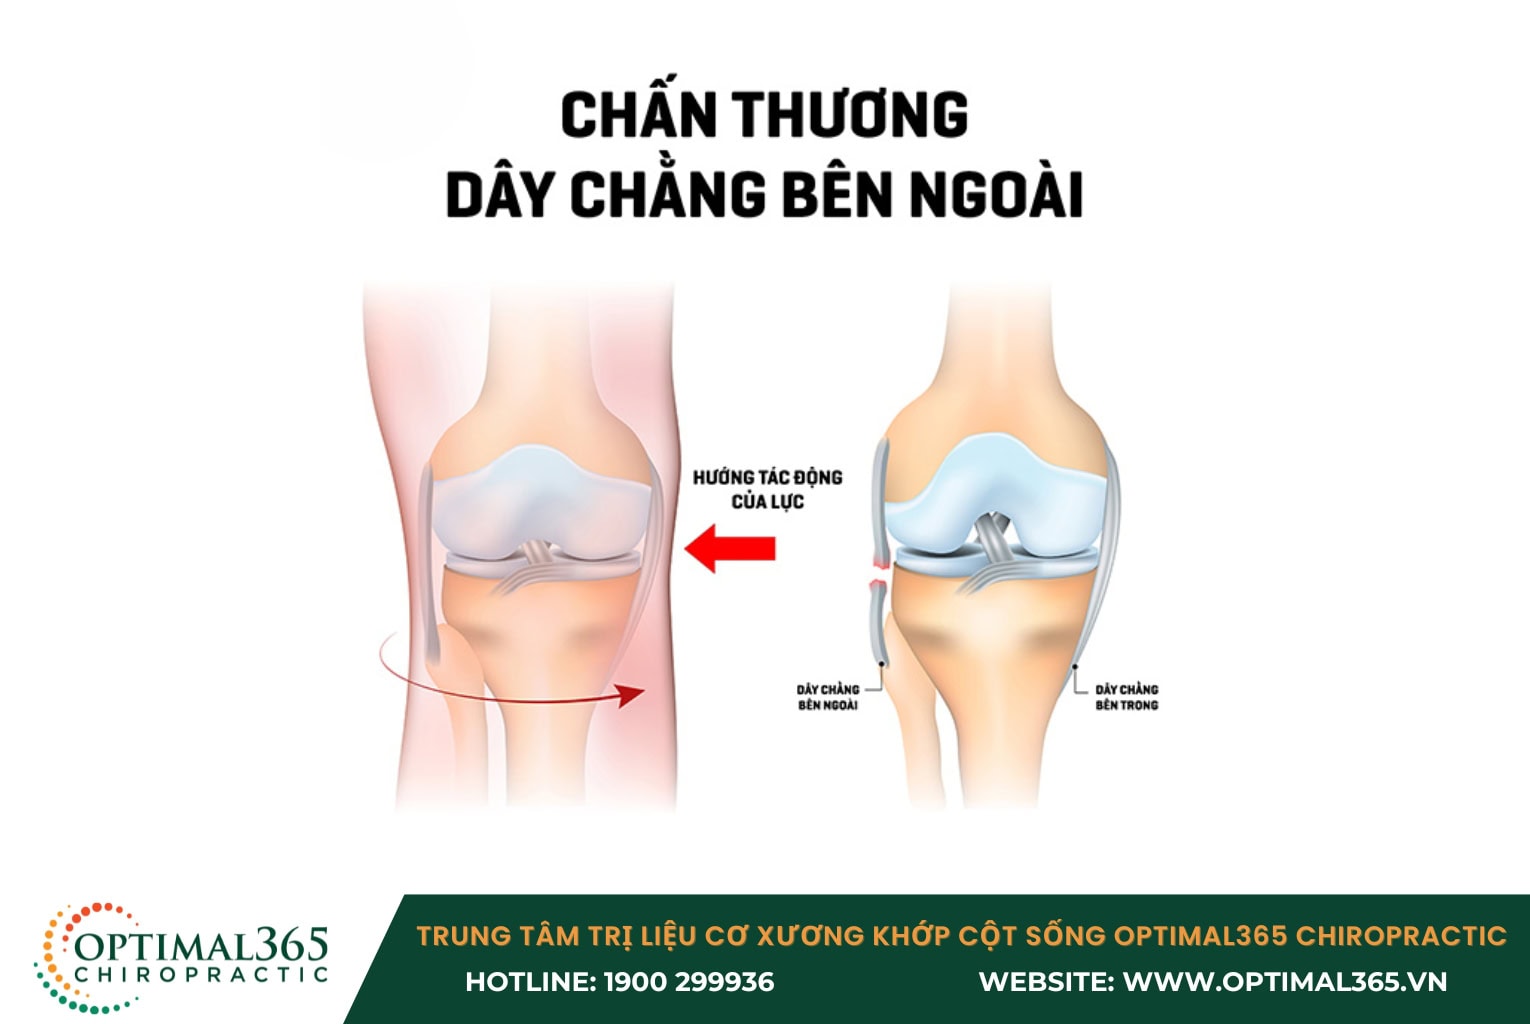

Chấn thương dây chằng đầu gối bên ngoài (LCL)

Dây chằng bên ngoài đóng vai trò quan trọng trong việc giữ cho mặt ngoài của khớp gối ổn định. Do đó, chấn thương đứt dây chằng bên ngoài thường xảy ra khi đầu gối bị tác động mạnh theo hướng “từ trong ra ngoài”, chẳng hạn như trong các va chạm thể thao hoặc tai nạn giao thông.

Triệu chứng chính của chấn thương LCL bao gồm:

- Đau dữ dội và căng cơ: Người bệnh cảm thấy đau nhói tại khu vực bên ngoài khớp gối, đặc biệt khi di chuyển hoặc chịu lực.

- Sưng tấy: Vùng đầu gối bị sưng lên nhanh chóng sau chấn thương, làm tăng khó khăn trong việc cử động.

- Mất ổn định khớp: Khớp gối trở nên lỏng lẻo, dẫn đến khó khăn trong việc duy trì thăng bằng và di chuyển, gây trở ngại cho các hoạt động sinh hoạt hàng ngày.